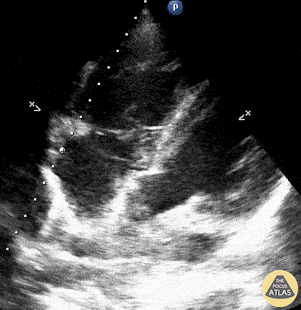

Pictured is an apical 4 chamber view of a patient who presented with sepsis secondary to lobar pneumonia and was found to have sepsis-induced cardiomyopathy. Appreciate both LV and RV systolic dysfunction. Johannes Achenbach